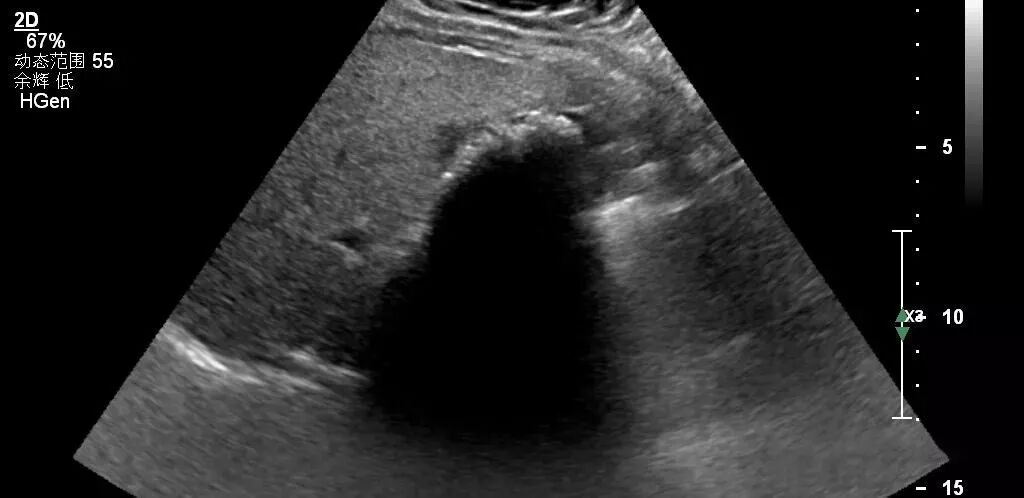

镜面伪像

声束斜射到声阻差很大的膈-肺界面时发生全反射而产生镜面伪像,这时膈下的为实像,膈下为虚像。

声像图上的虚像总是位于实像的深方。

图为肝脏内血管瘤的声像图,深方为血管瘤位于膈上的镜面伪像。